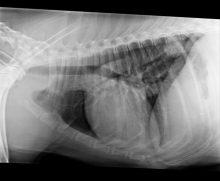

Chest Wall Deformities in Kittens (Pectus Excavatum)

Pectus Excavatum in Kittens Pectus Excavatum is a deformity of the chest wall where the caudal sternum deviates dorsally, ...